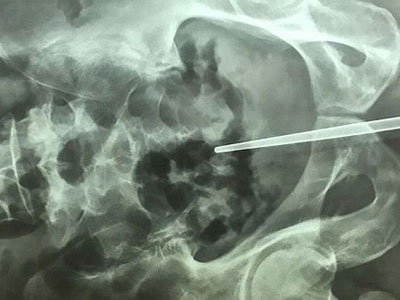

Giải cứu người đàn ông TQ bị kẹt “của quý” trong cờ-lê

Chàng trai dại dột bị mắc kẹt đũa trong "của quý"

Một chàng trai ở Trung Quốc phải nhập viện khẩn cấp sau khi làm mắc kẹt đũa trong “cậu nhỏ” của mình.